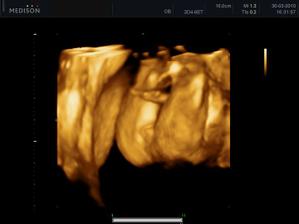

11.05. - (26+5) dnes jedeme na video

video se povedlo, máme asi 6 cca 5 - 10ti vteřinových videíí.Bylo to super. Karolínka se zase mlela jako drak. Je taková živoučká 😀